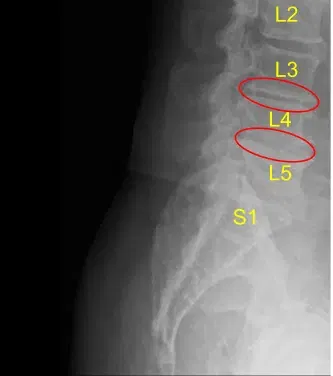

MRI and CT of his lumbar spine demonstrated severe degenerative disc space breakdown at L3-L4 and L4-L5 and accordingly they were offered a surgery for discogenic pain. The risks and potential benefits of surgery were extensively explained to the patient.

Disc space narrowing at L3-L4 and L4-L5

Disc bulge and facet arthropathy

They signed informed consent and were brought to the operating room for the aforementioned procedure. The findings of the preoperative lumbar spine x-ray are shown above and the patients also had a preoperative computerized tomography scan (CT scan) shown above.